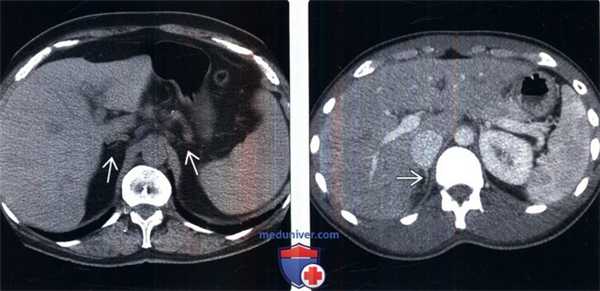

2. КТ при надпочечниковой недостаточности:

• Острая стадия: аддисонов криз, апоплексия надпочечников:

о Гетерогенные гиперденсные увеличенные (геморрагические) надпочечники

• Подострая стадия:

о Увеличенные надпочечники с пониженной плотностью (казеозный некроз или некроз)

• Хроническая стадия:

о Небольшие атрофичные надпочечники (аутоиммунный процесс)

о Плотные крупные кальцификаты (инфекция)

(Слева) У женщины 71 года с аутоиммунным полиэндокринным синдромом (недостаточность надпочечников, гипотиреоз) на бесконтрастной КТ выявлено уменьшение надпочечников Интересно, что данная пациентка также имела в анамнезе длительное течение саркоидоза, что служит дополнительной причиной первичной и вторичной (гипофизарной, гипоталамической) надпочечниковой недостаточности.

(Справа) Молодой мужчина с острой надпочечниковой недостаточностью, контрастная КТ: едва заметный правый надпочечник. После стимуляции козинтропином сывороточный кортизол не обнаружен.